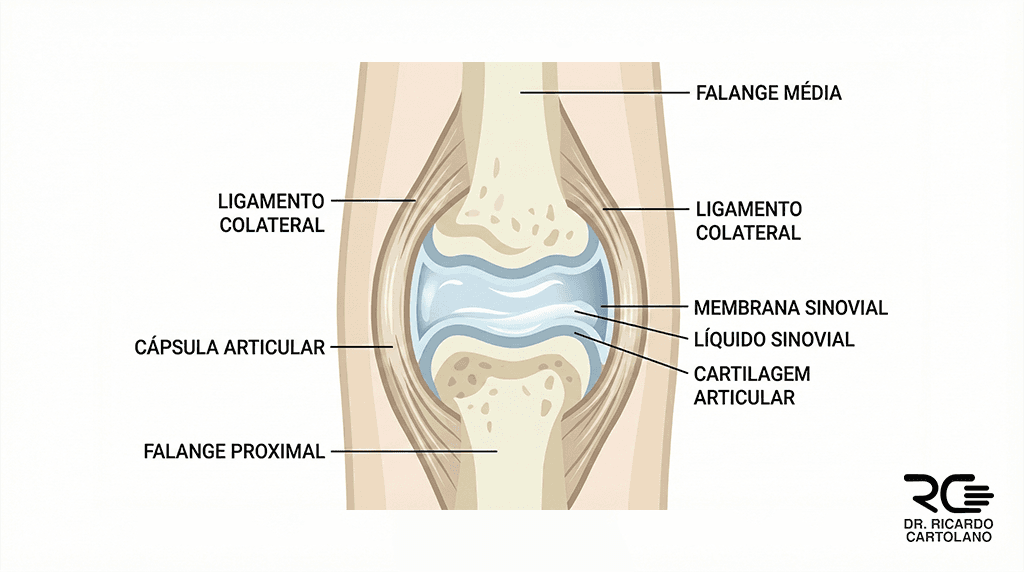

O que é uma Articulação?

A articulação é a ‘dobradiça’ que conecta dois ossos. Ela é uma estrutura complexa composta por cartilagem (que amortece o impacto), envolta por uma cápsula articular (um envelope impermeável) e estabilizada pelos ligamentos. No interior dessa cápsula, banhando tudo isso, existe o líquido sinovial: um fluido viscoso fundamental para nutrir a cartilagem e lubrificar o movimento, reduzindo o atrito.

Para que Servem os Ligamentos?

Os ligamentos são como cintas fibrosas, firmes e pouco elásticas, que prendem um osso ao outro. A função deles é estática: eles limitam o movimento para que ele não vá além do normal. São os ‘freios’ de segurança que impedem que o dedo ou punho dobrem para lados que não deveriam.